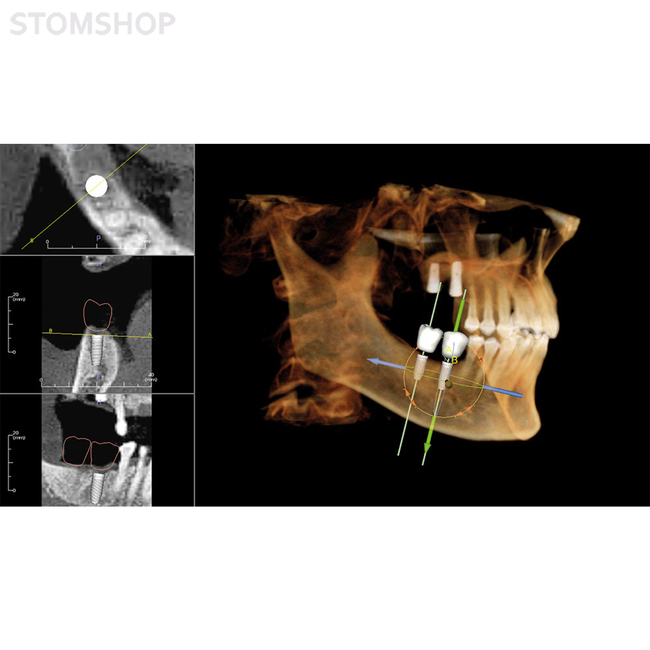

Имплантология: высокоточные планы имплантации

Необходимое вам программное обеспечение будет установлено в OP 3-D Vision во время эксплуатационного запуска. В перечне предустановленного ПО есть поддержка трехмерной рентгенографии, хирургические шаблоны для планирования имплантатов и имплантационной хирургии, другие варианты применения по выбору.

Ваша рентгенографическая система KaVo OP 3-D Vision готова для будущей эксплуатации: вы можете заказать DTX Studio, новую программную платформу, разработанную в виде целостной системы организации технологических процессов. DTX Studio постоянно оптимизируется и охватывает все области современной стоматологии и дентальной технологии в будущем. DTX Studio совместимо с операционными системами Mac и Windows. Оно будет объединять как уже существующие, так и проектируемые устройства многочисленных брендов, а также современные возможности программного обеспечения в объединенный рабочий процесс.